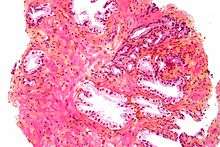

Microscopic glands of the prostate

The secretory epithelium is mainly pseudostratified, comprising tall columnar cells and basal cells which are supported by a fibroelastic stroma containing randomly oriented smooth muscle bundles that's continuous with the bladder. The epithelium is highly variable and areas of low cuboidal or squamous epithelium are also present, with transitional epithelium in the distal regions of the longer ducts.[8] Within the prostate, the urethra coming from the bladder is called the prostatic urethra and merges with the two ejaculatory ducts.[9]

Histology

- Glandular cells

- Myoepithelial cells

- Subepithelial interstitial cells[17]